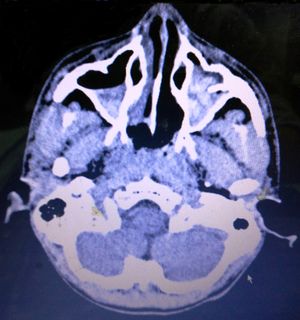

상악동 부비동염은 위턱굴, 즉 상악동에 생긴 염증을 말한다. 부비동염의 주요 증상으로는 염증이 생긴 부위 근처의 두통, 불쾌한 냄새가 나는 코나 목 분비물, 발열, 전신 쇠약감 등이 나타날 수 있다. 염증이 있는 부위의 피부는 만지면 아프거나(압통), 열감이 느껴지거나, 붉어지기도 한다. 방사선 사진을 찍어보면 정상적으로 공기가 차 있어 검게 보여야 할 상악동이 염증으로 인한 점액 저류 때문에 불투명하게 보이거나 뿌옇게 나타난다.[7]